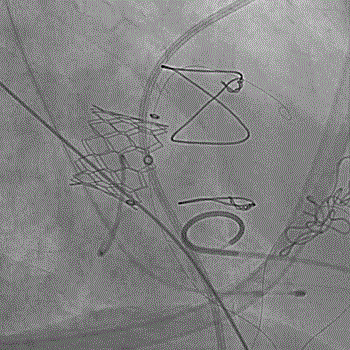

经过手术团队充分讨论病例资料,模拟在首次手术生物瓣环与第二次手术瓣膜内植入定位更精准的佰仁Renato®球扩式瓣中瓣,以有效治疗二尖瓣自膨式介入瓣毁损。手术按照术前讨论方案进行,过程顺利,成功植入27号Renato®球扩瓣,瓣膜植入位置理想,启闭功能表现出色。左室造影及经食道超声观察无明显瓣中及瓣周反流,平均跨瓣压差降至8.0mmHg。

球扩瓣释放